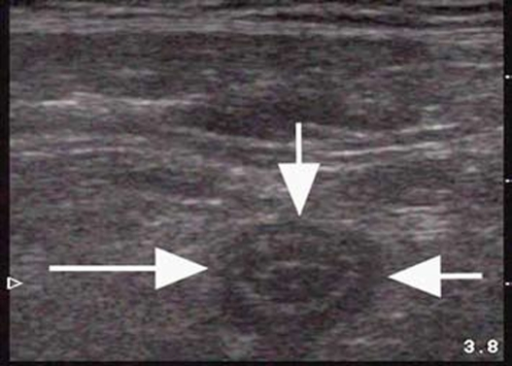

Appendicitis in short axis

| current | 22:06, 22 March 2015 | ![]() | 512 × 366 (331 KB) | Neil.m.young (Talk | contribs) | Appendicitis in short axis Acquired from: OPENi - An Open Access Biomedical Search EngineAn Open Access Biomedical Image Search Engine |